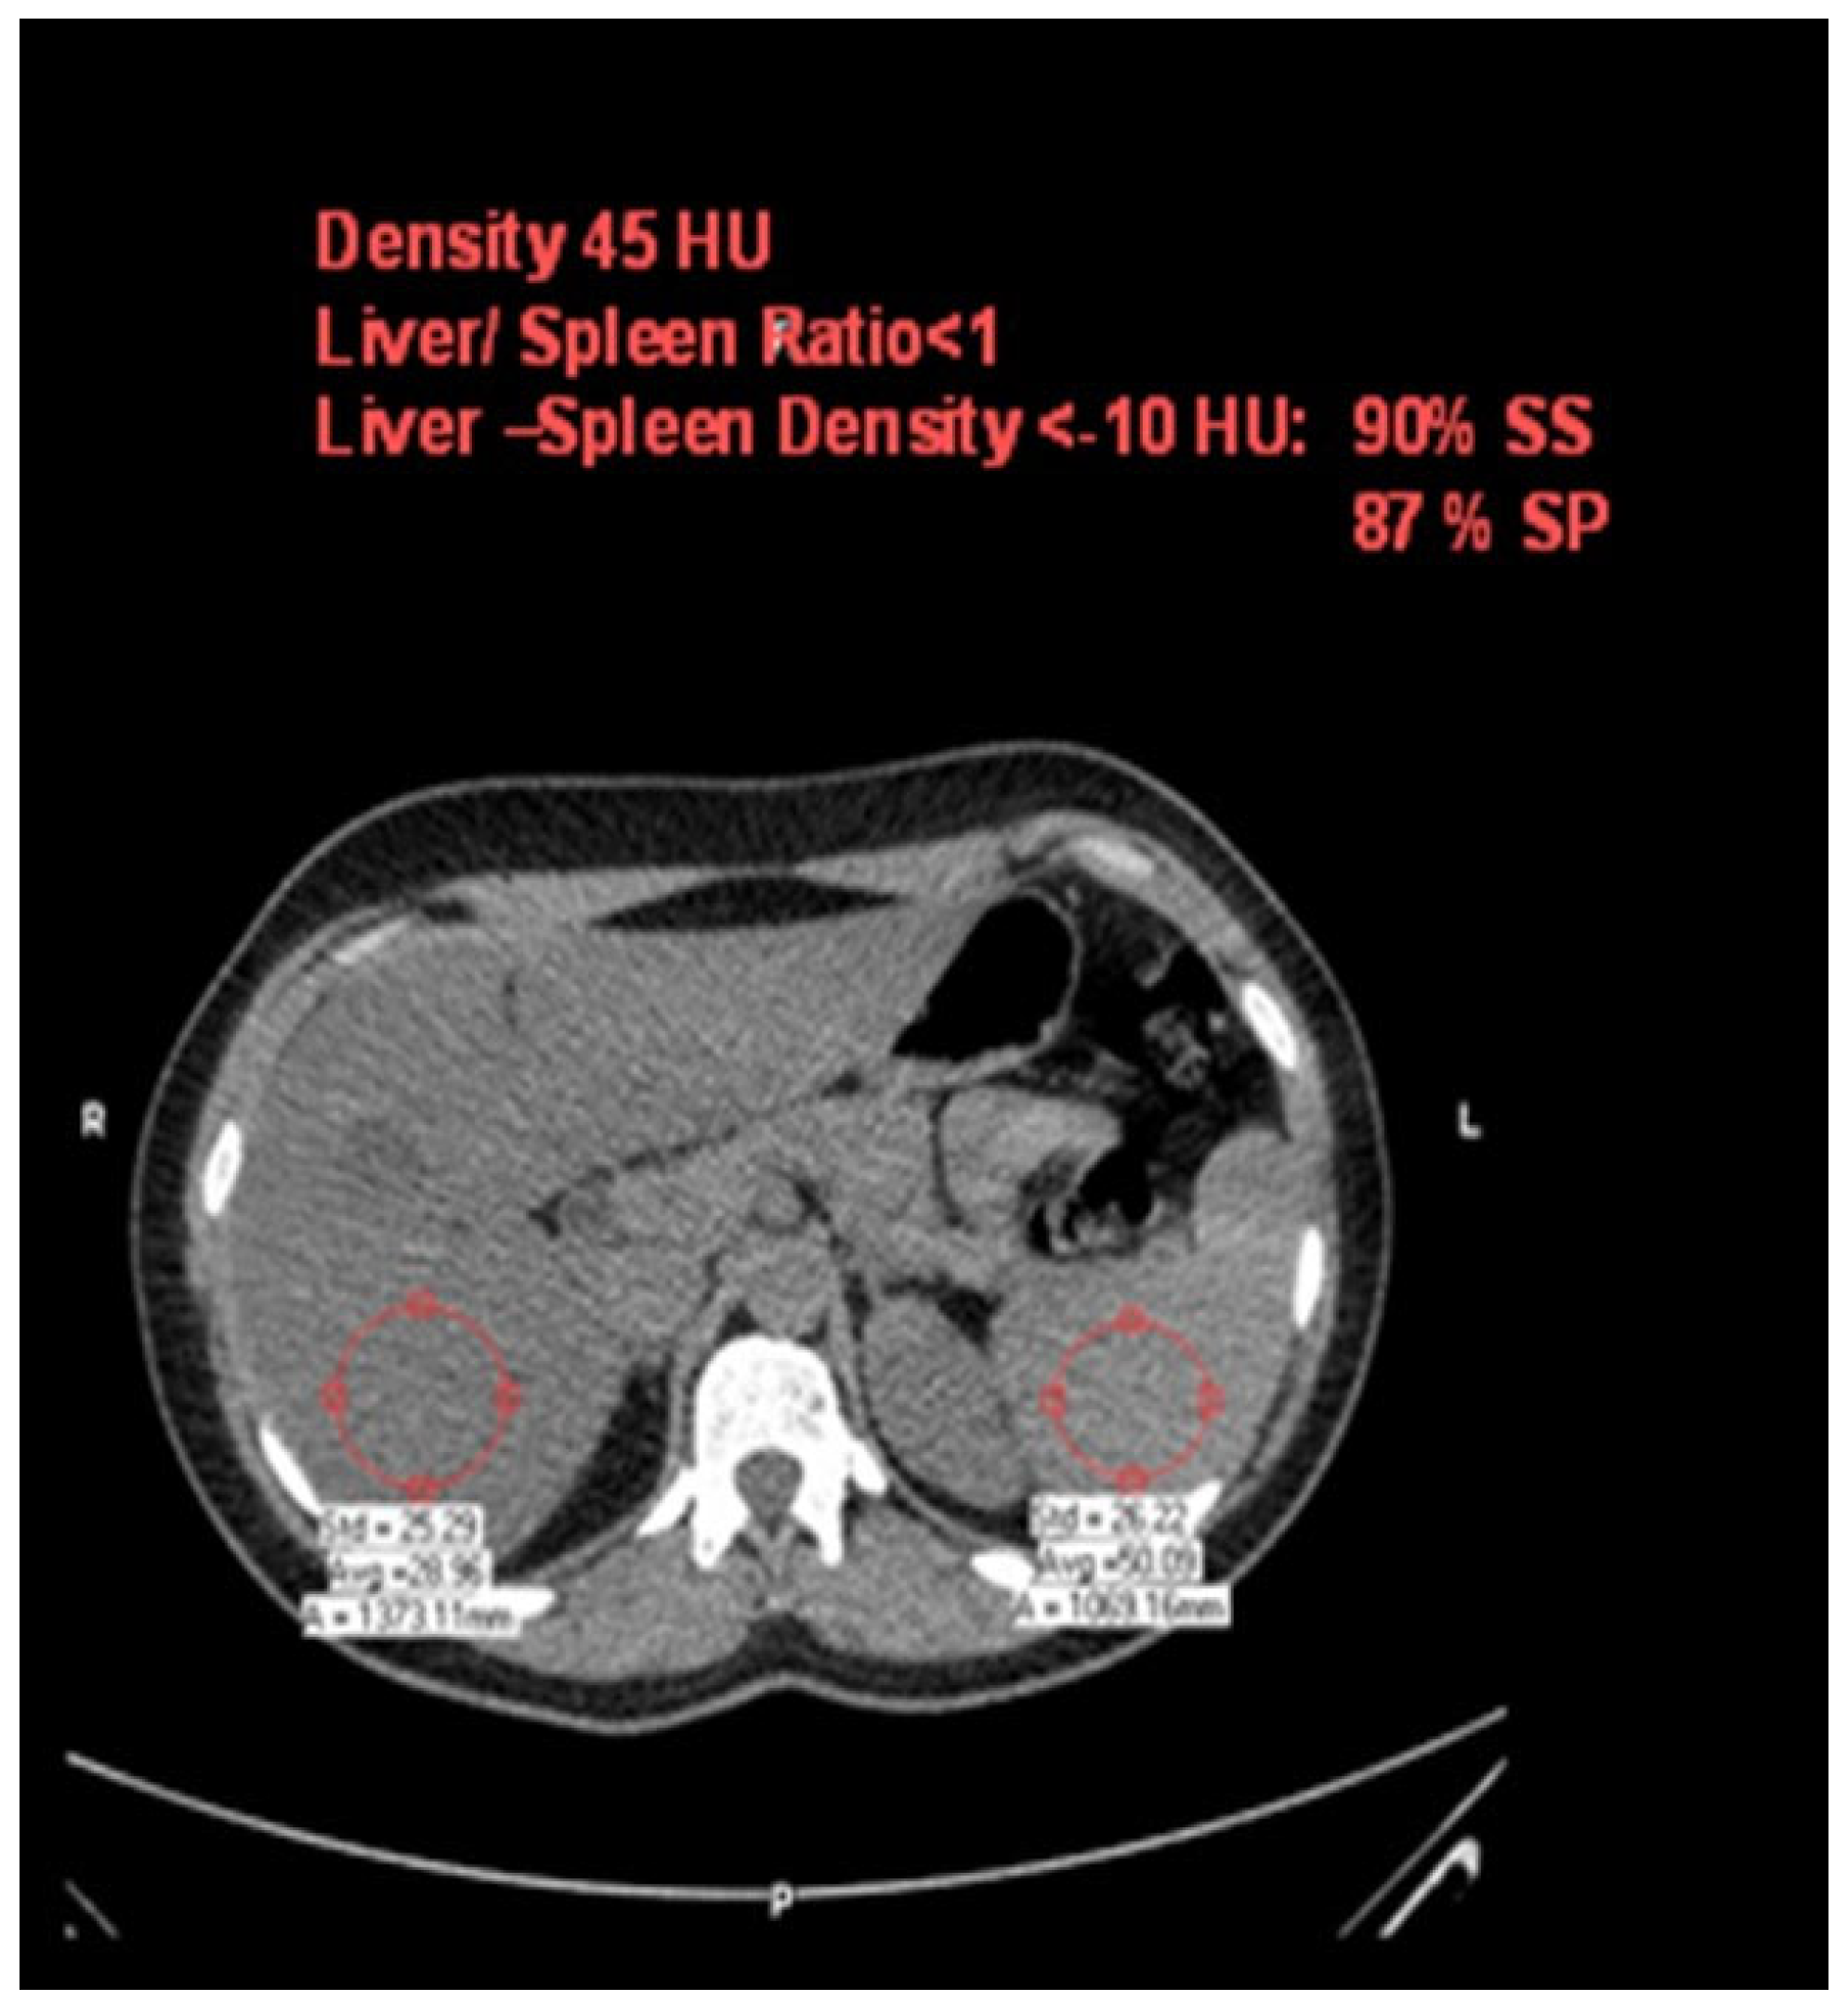

2.4. Hepatic Steatosis

Hepatic steatosis diagnosis was defined as attenuation of at least –10 HU (calculated as liver attenuation minus spleen attenuation) detected using CT [23]. The measurement of liver and spleen attenuation was performed in a blinded way. Hepatic attenuation was measured by randomly selecting three circular regions of interest (ROI) on three transverse sections at different hepatic levels. The ROI values were averaged as the mean hepatic attenuation. To provide an internal control, the mean splenic attenuation was calculated by also randomly averaging three ROI values of splenic attenuation on three transverse sections at different splenic levels (Figure 2).

Figure 2.

Computed-tomography section showing liver and spleen attenuation.

One limitation of the study is that the diagnosis of fatty liver was performed with non-enhanced CT rather than liver biopsy. However, a cutoff of liver–spleen density ≥ −10 HU identifies patients with diffuse fatty liver with 87% sensitivity and 90% specificity [23]. Another limitation is that fibro-scans and Fib-4 were not used in this research study, although other accurate tests were performed. The small number of the cohort in this single-center study warrants the further assessment of this issue in multi-center settings and with a wider cohort range.